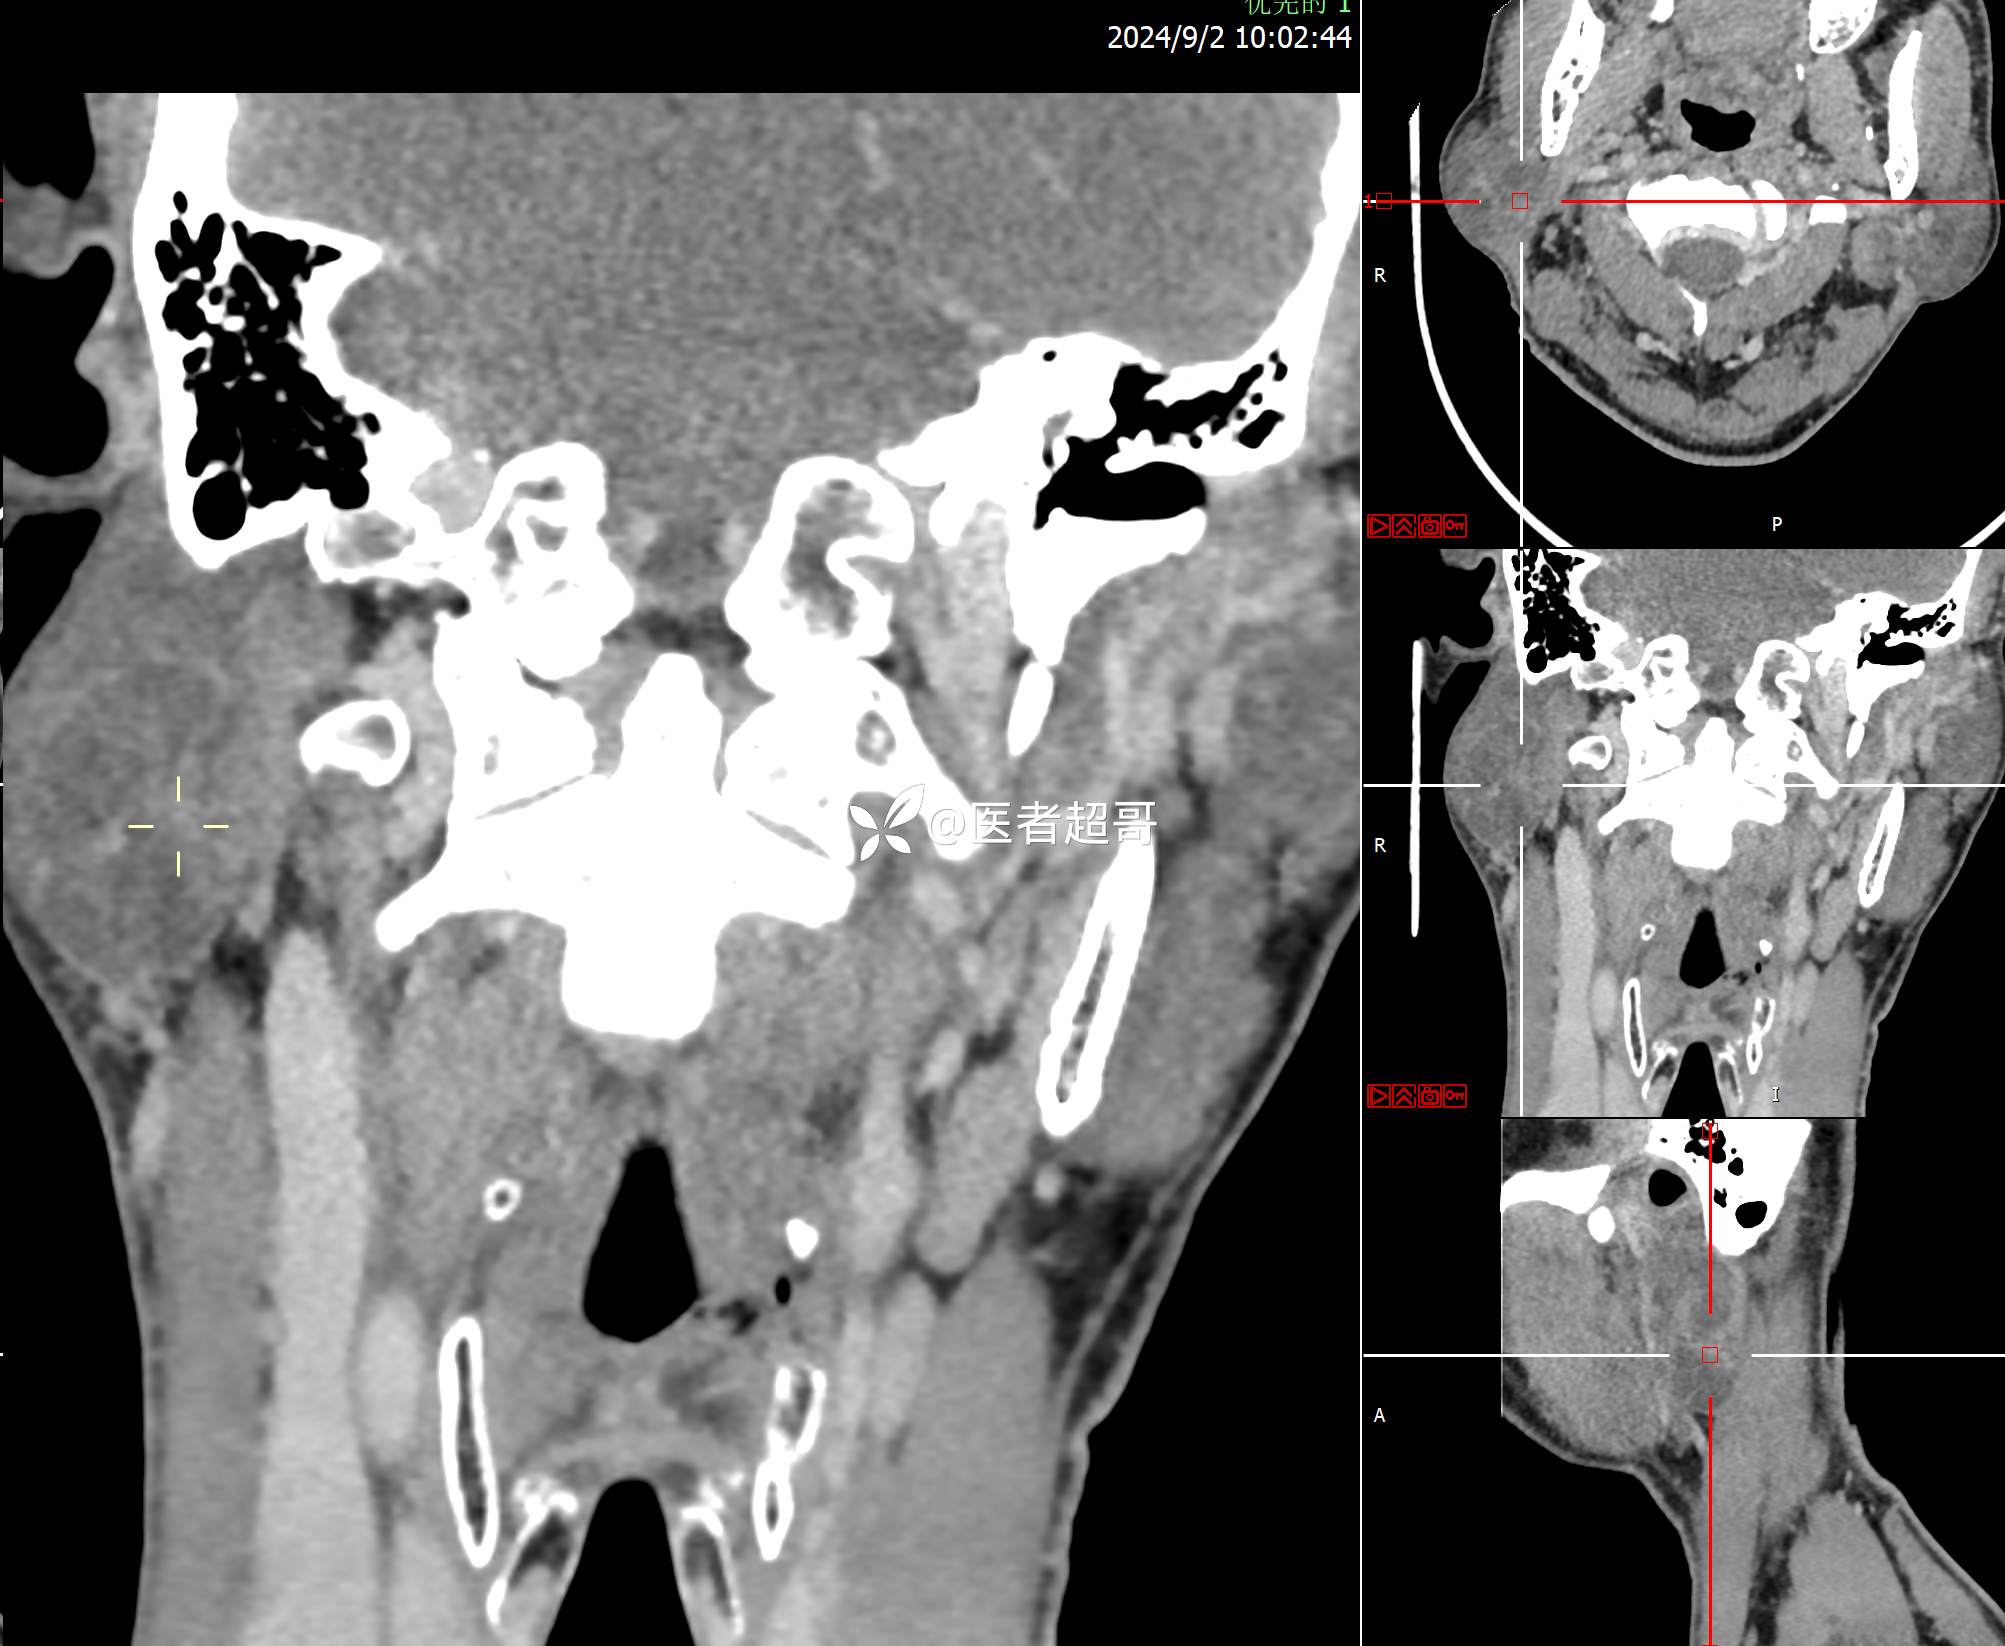

腮腺肿物,CT、MRI齐全,情诊断分析,有详细术程及病理!

主诉:发现右腮腺肿物6个月。

现病史:患者于6个月前无明显诱因发现右侧腮腺区肿物,无疼痛,无局部皮肤破溃,无吞咽困难,无听力下降,无发热,无头痛头晕,患者自发病后在外未治疗,6天前于当地卫生院检查建议手术,为求手术治疗,来我院就诊,门诊以“腮腺肿瘤(右)”收入我院。患者自发病以来,神志清楚,精神可,饮食可,睡眠可,大便正常,小便正常,体重无明显变化。